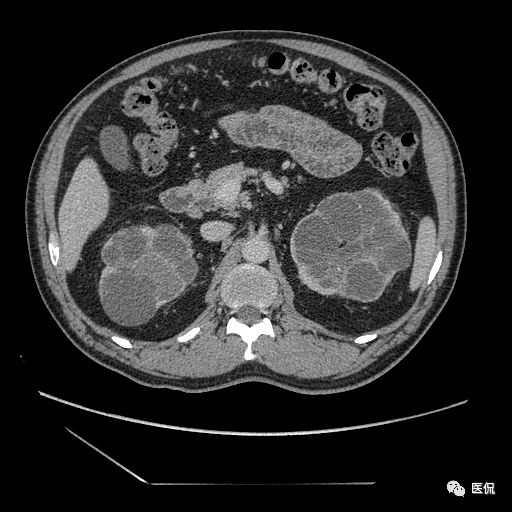

双肾实质可见多发囊性密度灶,其内密度不均匀,并可见钙化灶,增强扫描未见明显强化灶。肾周脂肪间隙清晰,与邻近组织分界清楚。

多囊肾的 CT 表现主要表现为双肾增大,轮廓光滑或有分叶,肾实质内多个大小不等的囊肿呈蜂窝状,多呈水样低密度,增强扫描囊肿本身无强化,而囊肿间正常肾组织增强,对比明显。当囊肿张力过高,使囊壁上毛细血管牵拉破裂出血时,表现为囊肿内稍高密度影,随访CT 值减低。囊壁钙化,表现为点线状高密度影像,随访CT值无变化。有文献报道约 30%病例可并发多囊肝或多囊胰。